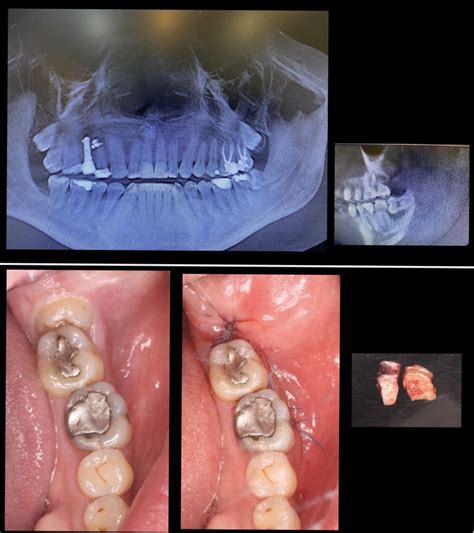

- Extracción de la muela: Una vez estés bien anestesiado (comprobamos que no sientes dolor antes de empezar), procedemos a extraer la muela del juicio. Si es una extracción simple, el proceso es bastante directo: utilizamos un instrumento llamado elevador o botador para aflojar el diente con movimientos suaves, y luego unas fórceps (pinzas dentales) para sujetar la muela y sacarla con cuidado. Sentirás presión y movimiento, pero nada de dolor. Muchas veces la muela sale completa de una vez. En cambio, si la muela está impactada o sale en mala posición, la extracción se vuelve quirúrgica: haremos una pequeña incisión en la encía para descubrir la muela. Es posible que necesitemos remover un poco de hueso alrededor con una fresa (un torno especial) para liberar el diente. A veces también cortamos la muela en partes más pequeñas para sacarla por secciones, especialmente si la corona (la parte de arriba) es grande o las raíces están enganchadas. Todo esto suena aparatoso, pero recuerda: tú estarás anestesiado localmente, no sentirás dolor, solo los movimientos y vibraciones.

- Cierre y cuidados inmediatos: Cuando la muela del juicio ya está fuera, queda una pequeña herida en la encía (y a veces un espacio en el hueso). Si fue una extracción simple, normalmente no hace falta dar puntos; la herida es pequeña y tu propia sangre formará un coágulo que protege y empieza la cicatrización. En extracciones quirúrgicas, colocaremos puntos de sutura (muchas veces puntos reabsorbibles que no hay ni que quitar; otros se retiran en aproximadamente 7 días). Tras la extracción, se coloca una gasa sobre la zona y te pediremos que la muerdas firmemente durante 20-30 minutos. Esto ayuda a contener el sangrado inicial y a que se forme el coágulo correctamente.